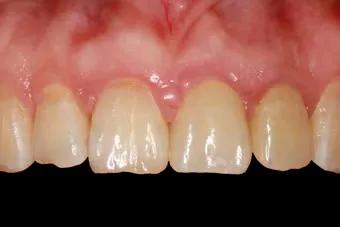

与活动假牙、烤瓷牙牺牲周围牙齿保全自己的做法相比,种植牙是能和真牙打成一片的。

种植牙是将种植体(金属钛,可与人体结合)放入缺牙区的牙槽骨充当人工牙根,不依靠邻牙就能站稳脚跟。

种植牙形态美观、舒适、固位稳定,功能与天然牙近似,能高效地行使咀嚼功能,且无需磨损旁边的牙齿,对邻牙没有任何伤害。

无需活动牙类似的卡环或基托,没有异物感,寿命长,只要不是遇人不淑没种好,种上的牙齿至少能用30余年。